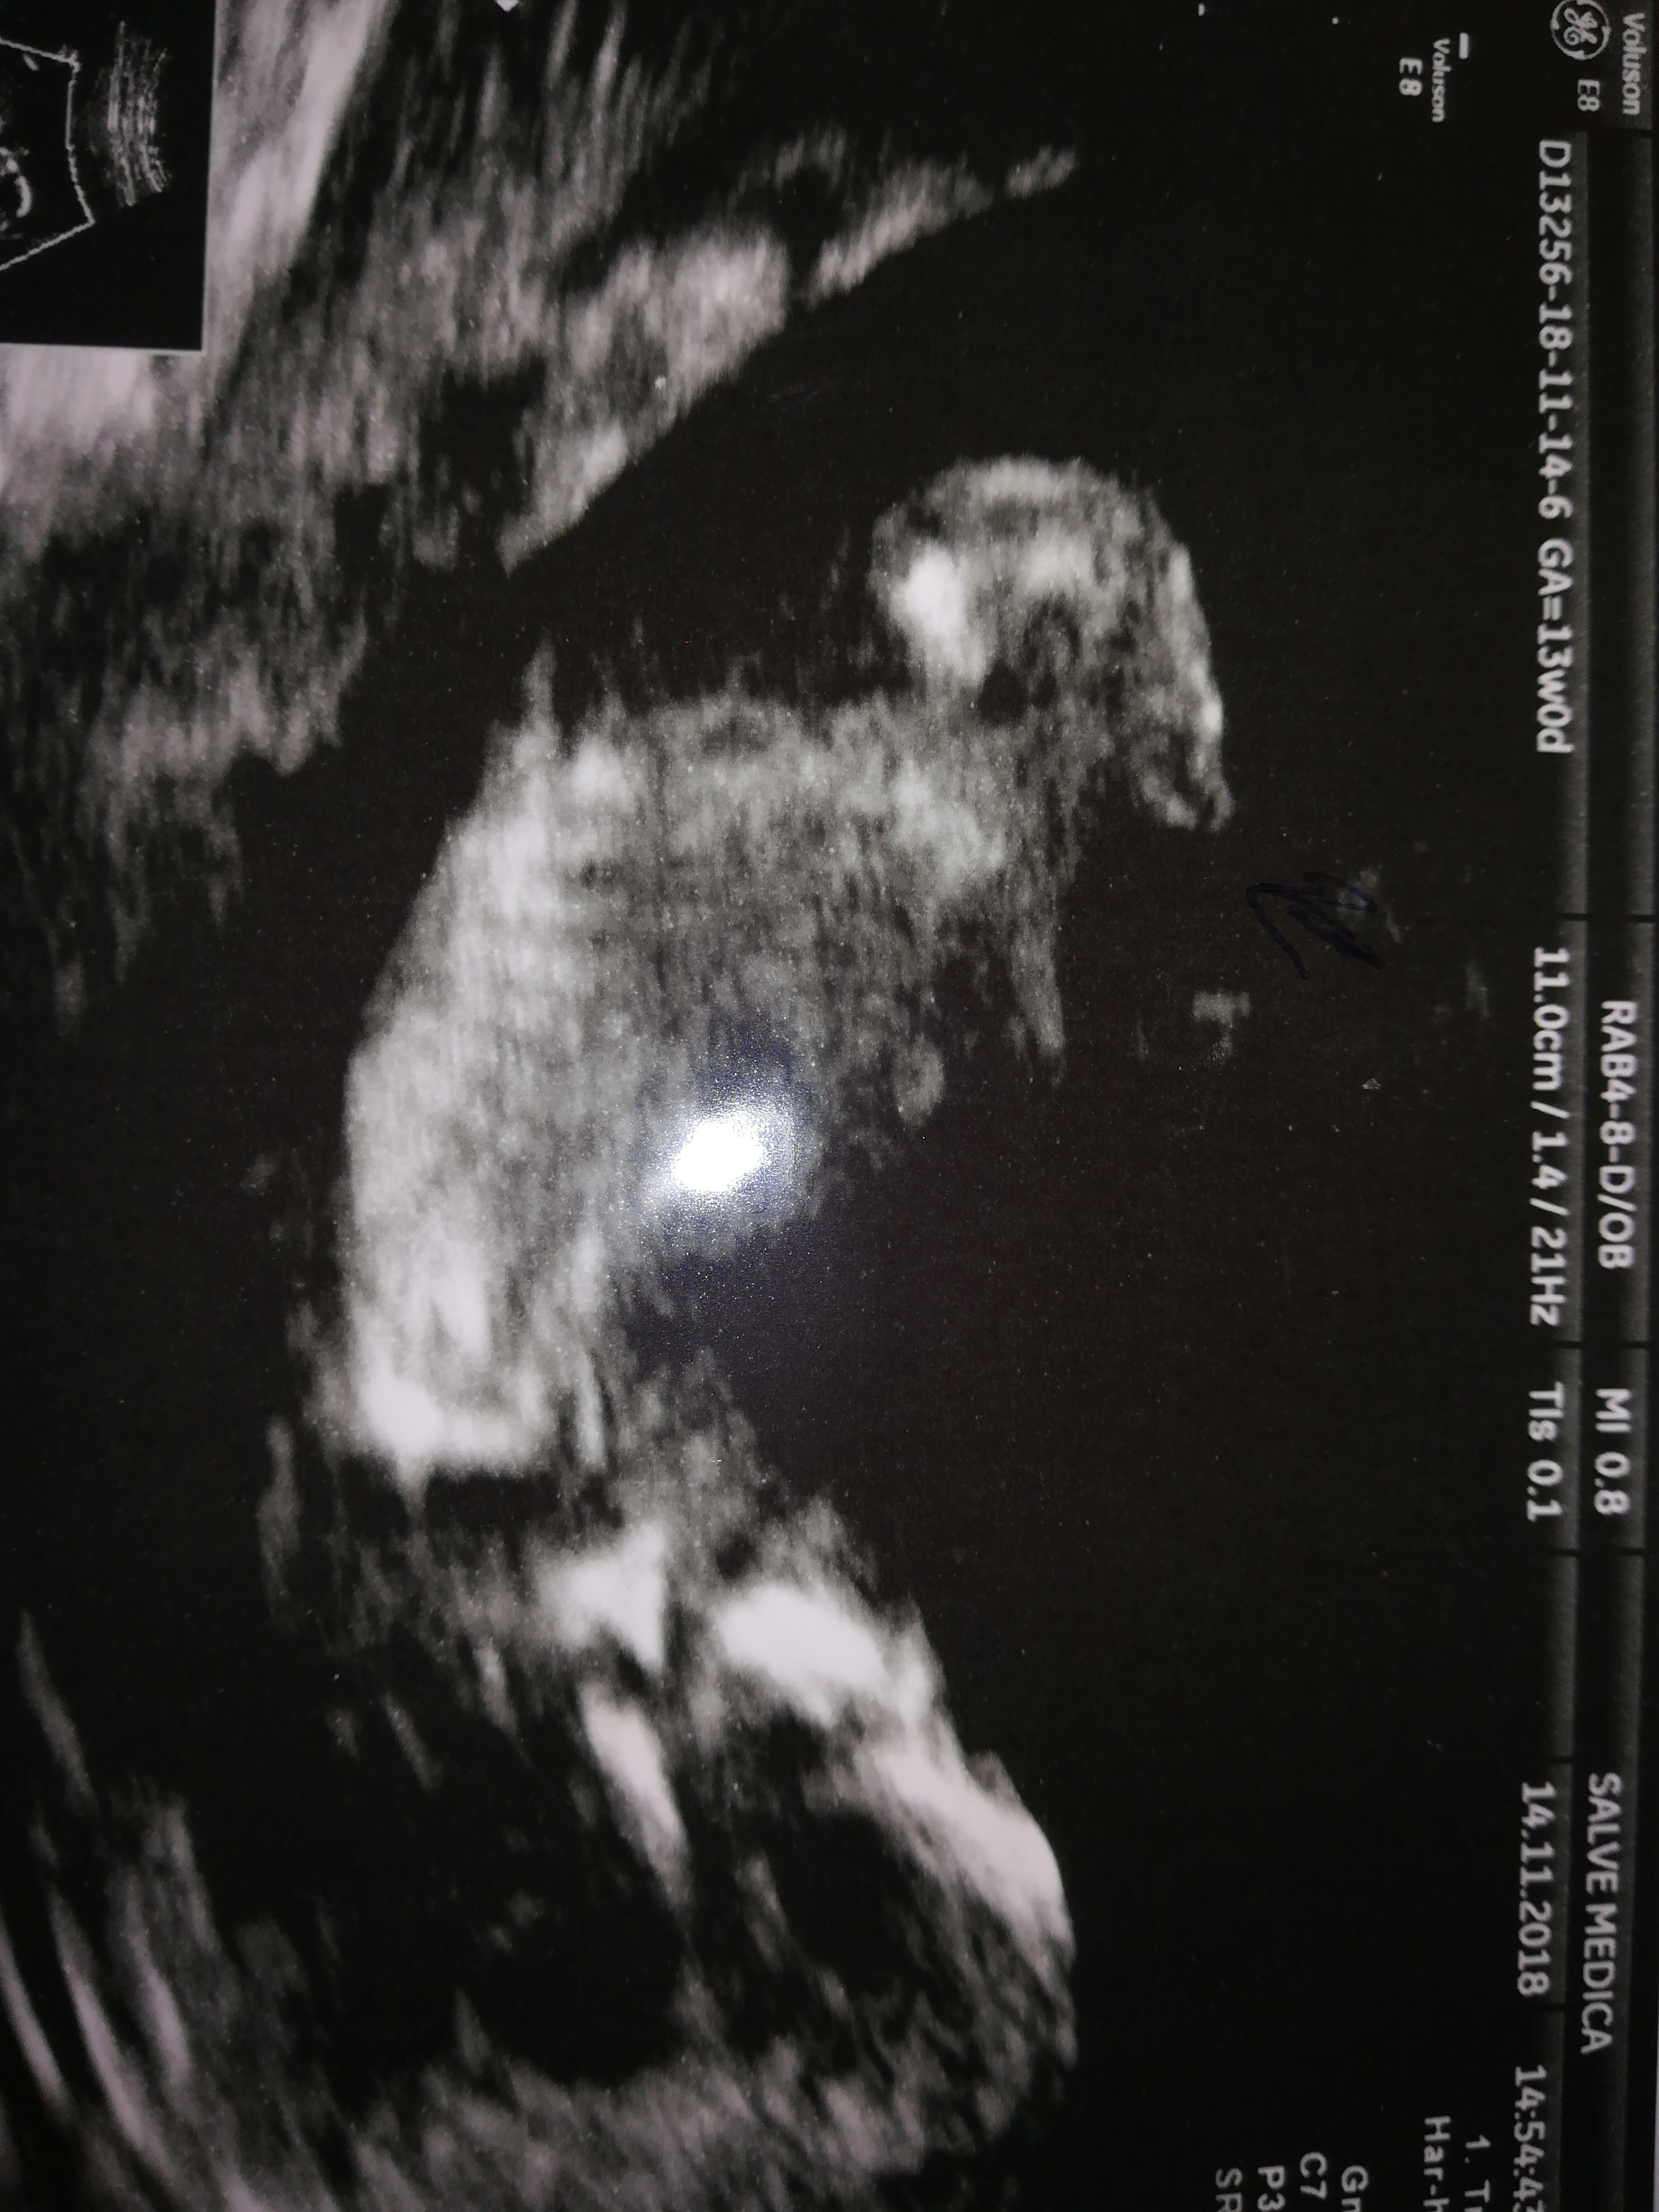

Jestem po usg genetycznym 13 tydzień pani doktor twierdzi że chłopak. Myślicie że się nie myli?

Załączniki

• 15427980879626744821817313785734.jpg

15427980879626744821817313785734.jpg

1,3 MB · Wyświetleń: 395

• 15427981771403861325230487947264.jpg

15427981771403861325230487947264.jpg

1,3 MB · Wyświetleń: 390

Maziajka może teraz coś lepiej widać? Doktor zaznaczyła strzałka niby siusiaka.